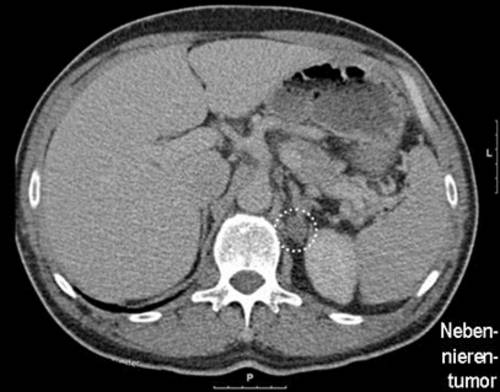

Tumor an der nebenniere. Tumore der Nebenniere Die beiden Nebennieren Glandulae suprarenales liegen jeweils am oberen Pol der beiden Nieren. Ich denke man sollte ihn im Verlauf kontrollieren und nur bei entsprechender Wachstumstendenz operativ angehen. Der häufigste bösartige Tumor der Nebenniere ist das Nebennierenrindenkarzinom adrenokortikales Karzinom.

10-20 der Menschen weisen Adenome der Nebennieren auf die heutzutage zunehmend häufig als Zufallsbefund entdeckt werden. Hyperaldosteronismus Conn-Syndrom Vermehrte Glukokortikoidbildung Morbus Cushing in Folge vermehrter Ausschüttung des Nebennierenrinden-stimulierenden-Hormons ACTH. _ Ein Tumor an der Nebenniere wird wenn überhaupt in der Regel zufällig bei einer bildgebenden Untersuchung entdeckt.

In den Nebennieren kleinen Hormon-produzierenden Drüsen die direkt an den Nieren anliegen aber an deren Funktion völlig unbeteiligt sind können Tumore. Man geht davon aus dass bis zu 3 aller erwachsenen gesunden Personen einen Tumor in der Nebenniere hat wobei die Häufigkeit im Laufe des Alters zunimmt. Von einem inzidentellen adrenergen Tumor spricht man immer dann wenn er rein zufällig in der Bildgebung auffiel die nicht aufgrund einer möglichen Nebennierenerkrankung durchgeführt wurde.